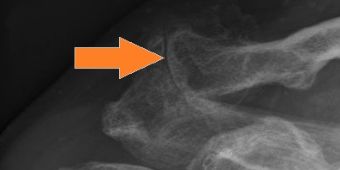

acg-arthrose-roe

Schultereckgelenksarthrose mit aufeinanderreibenden Knochenenden (Pfeil).

Das Schultereckgelenk verbindet das Schlüsselbein mit dem Schulterdach und wird vor allem bei Überkopfbelastungen und axialer Kompression wie beim Bankdrücken oder beim Liegestütz beansprucht. Im Gelenk befindet sich ein Faserknorpelinterponat, das Zug-, Druck- und Scherkräfte abfängt und auf beide Gelenkpartner verteilt. Mit zunehmendem Alter kann sich der Gelenkknorpel abnützen, was zu einem Aufbrauch des Gelenkspaltes und Knochenanbauten, der sog. Schultereckegelenksarthrose (Bild) führt.

Diagnostik: Einschränkung von Überkopfbewegungen

Therapie: Wiederherstellung des Gelenkspaltes